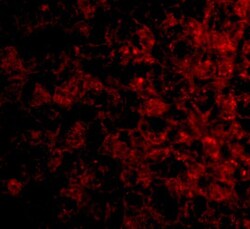

Supportive validation

- Submitted by

- Invitrogen Antibodies (provider)

- Main image

- Experimental details

- Immunohistochemistry of TSLP-R in human liver tissue with TSLP Receptor Polyclonal Antibody (Product # PA5-20378) at 5 µg/mL.

- Immunofluorescence of TSLP Receptor in Human Liver tissue with TSLP Receptor Polyclonal Antibody (Product # PA5-20378) at 20 µg/mL.